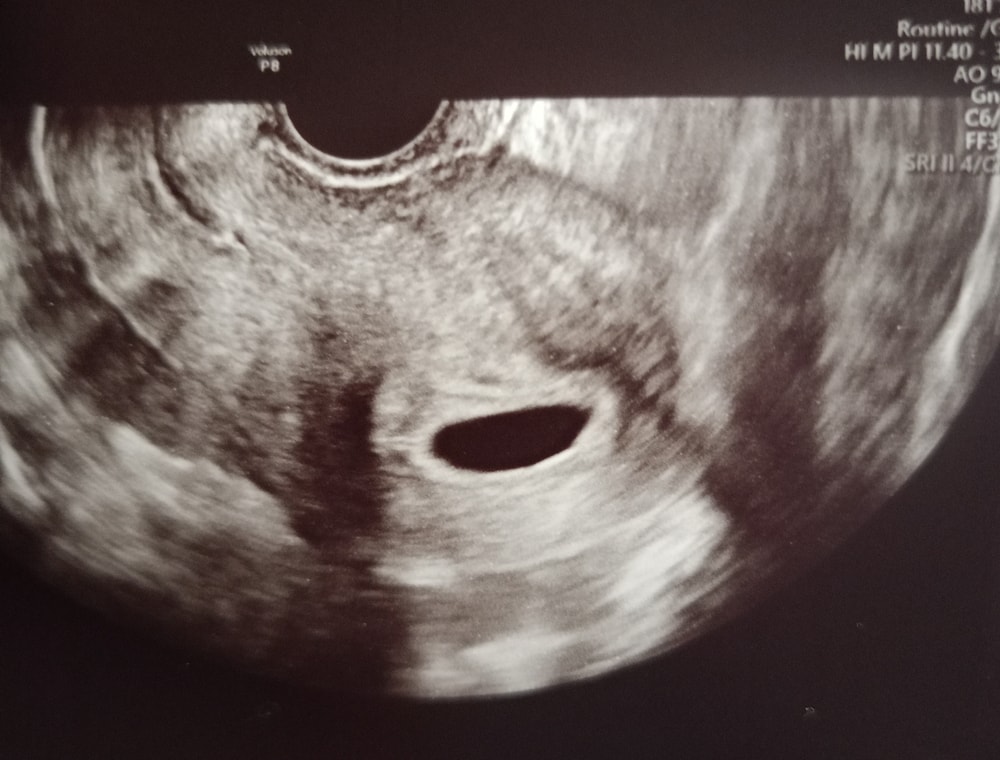

Ну что ж, у моей истории, видимо хорошего конца не будет. На УЗИ думала сначала сходить, когла будет недель 8-9, но начиталась про всяких пузырных заносов и решила всё де провериться. Итак,плодное яйцо опережает срок по месячным на неделю и оно пустое... В заключении - повторить УЗИ через неделю, предполагается анэмбриония. Пошла в "женскую" больницу, сказали - вакуум, нужно госпитализироваться и лучше не тянуть, тк опасно кровотечением. Признаков, что что-то прерывается вообще нет. Теперь даже не знаю стоит ждать эту неделю или нет. В приёмном покое сказала, ну можете в пт у нас сделать УЗИ и спуститесь к нам га госпитализацию.. По поводу моего состояния - когда принимаешь как всё есть, нет ни слез, ни переживаний, ни волнений, просто нужно решить вопрос который есть, повлиять тут я ни на что не могу.